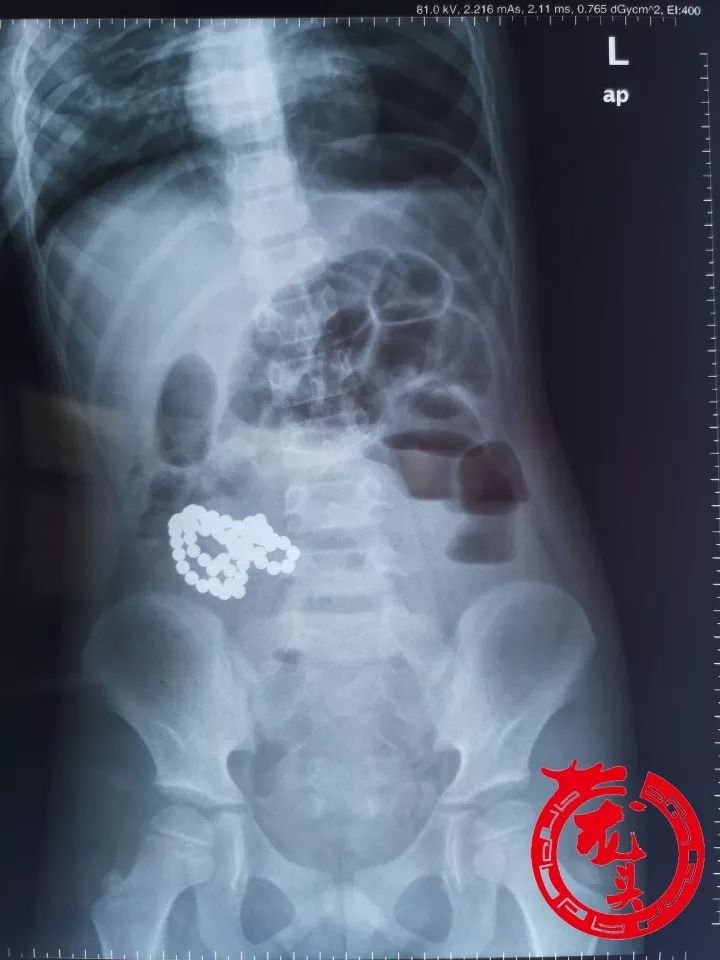

「注意」哈尔滨6岁男童肚子里竟多了61个"球"!家长肠子都悔青了